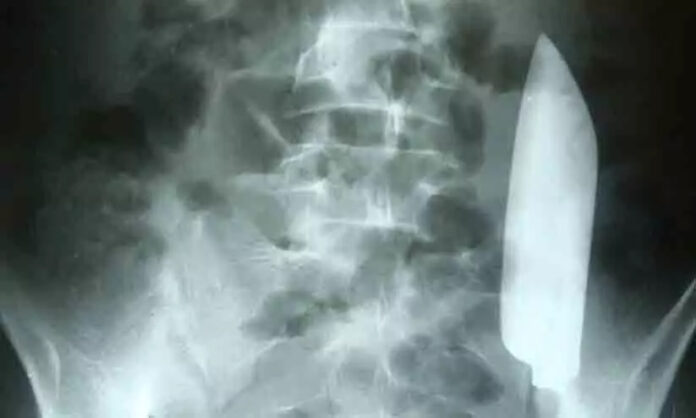

കാഠ്മണ്ഡു: കടുത്ത വയറുവേദനയുമായെ ആശുപത്രിയിലെത്തിയ 22 കാരന്റെ വയറ്റിൽ നിന്ന് പുറത്തെടുത്തത് 15 സെ.മി വലിപ്പമുള്ള കത്തി. ദിവസങ്ങൾക്ക് മുമ്പ് യുവാവിന് കത്തിക്കുത്തേറ്റിരുന്നതായി ന്യൂസ് വീക്ക് റിപ്പോർട്ട് ചെയ്തു. എന്നാൽ കത്തി വയറ്റിനുള്ളിലുണ്ടെന്ന കാര്യം ആരും സംശയിച്ചിരുന്നില്ല.

കത്തി ശരീരത്തിനുള്ളിൽ എത്തിയതിന്റെ പാടുകളൊന്നും പുറത്ത് കാണാനുമുണ്ടായിരുന്നില്ല. കത്തി പുറത്തെടുത്ത് മുറിവ് ​തുന്നിക്കെട്ടി യുവാവ് വീട്ടിലെത്തി.

മദ്യപിച്ച അവസ്ഥയിലാണ് യുവാവിന് കുത്തേറ്റത്. അതിനാൽ അപ്പോൾ എന്താണെന്ന് സംഭവിച്ചത് എന്ന് ഓർത്തെടുക്കാനുമായില്ല. പിറ്റേ ദിവസം മുതൽ വയറ്റിൽ കഠിനമായ വേദന അനുഭവപ്പെട്ടു. എന്നാൽ ക്ഷീണമോ തളർച്ചതോ ഛർദിയോ മലബന്ധമോ ഒന്നും അനുഭവപ്പെട്ടിരുന്നില്ല. രക്തം പരിശോധിച്ചപ്പോഴും പ്രശ്നങ്ങളുണ്ടായിരുന്നില്ലെന്ന് ഡോക്ടർമാർ പറഞ്ഞു.

ഡോക്ടർ ശരീരം സൂക്ഷ്മമായി നിരീക്ഷിച്ചപ്പോഴാണ് മുറിവിന്റെ പാട് കണ്ടത്. തുടർന്ന് എക്സ്റെ എടുത്തപ്പോൾ വയറ്റിൽ കത്തിയുള്ളതായി കണ്ടെത്തി. ഇത് വയറിന്റെ നിന്ന് ഒരുഭാഗത്ത് നിന്ന് മറ്റൊരു ഭാഗത്തേക്ക് മാറുമ്പോഴാണ് വേദന അനുഭവപ്പെട്ടത്. ശസ്ത്രക്രിയ വഴിയാണ്കത്തി പുറത്തെടുത്തത്.